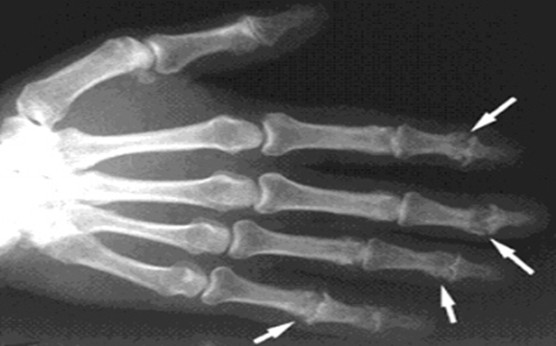

Диагноз можно установить после проведения рентгенографии пораженного сустава. Также возможно использование ультразвукового исследования для обнаружения воспалительных процессов в суставах и окружающих тканях.